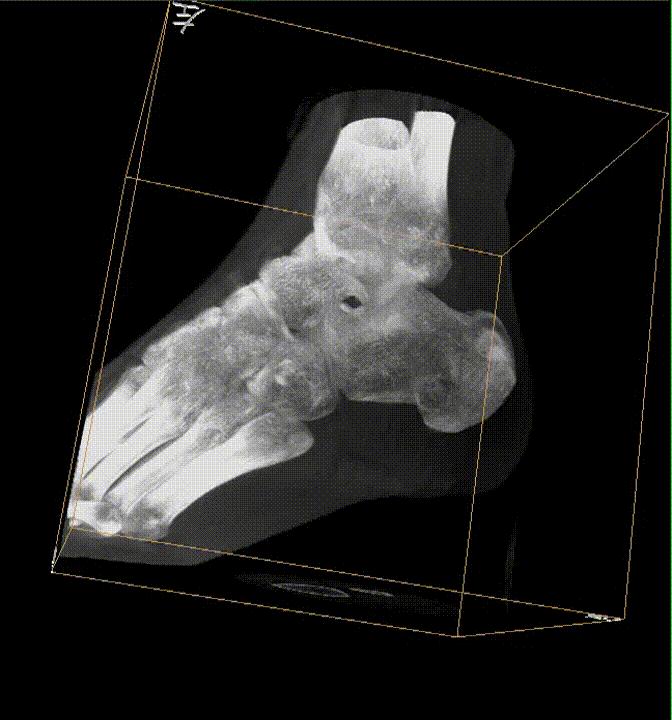

踝关节骨折通常为关节内的骨折。关节内的骨折在做手术的时候通常要做到解剖复位,就是说要把受伤的骨头复位成和没受伤的时候一模一样,只有这样才能有更好的预后,避免患者术后的并发症。所以对手术的要求是非常高的。